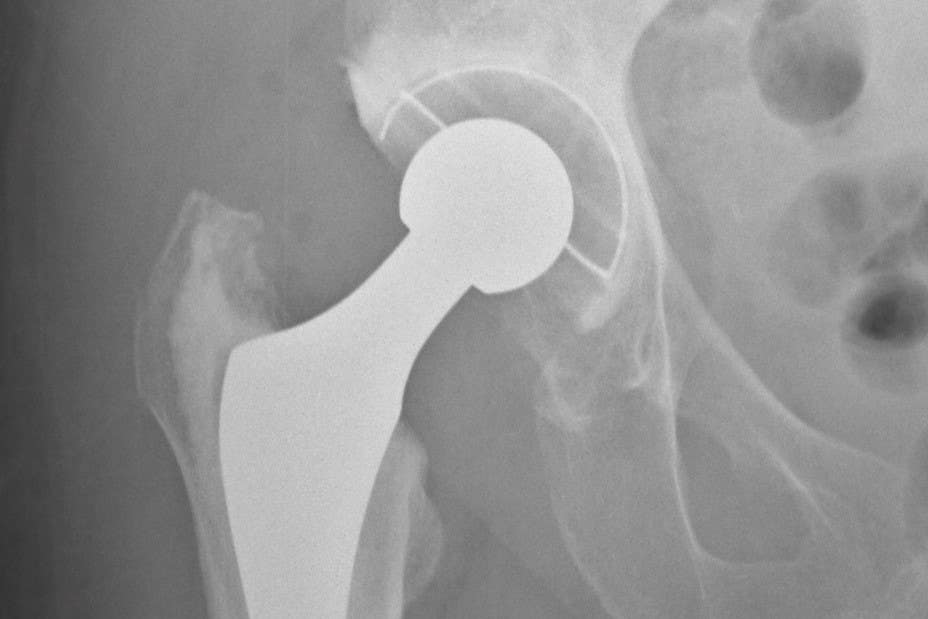

Smith & Nephew’s business lines include orthopaedics, where it makes high-tech knee and hip implants used to replace damaged or worn joints.